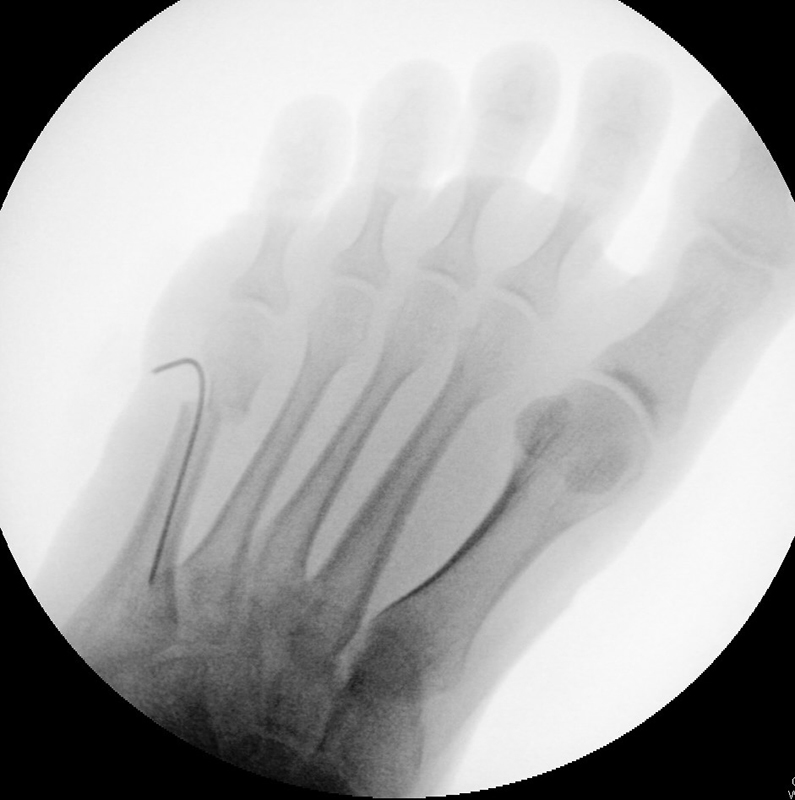

Abb. 2 a-c: offene Wachstumsfugen MT I Basis und Zehen (a), teilweise geöffnete Wachstumsfugen (b) und geschlossene Wachstumsfugen (c).

Zum Lesen der Bildbeschreibung und zur Vollansicht bitte die Bilder anklicken. Bilder: A. Helmers.